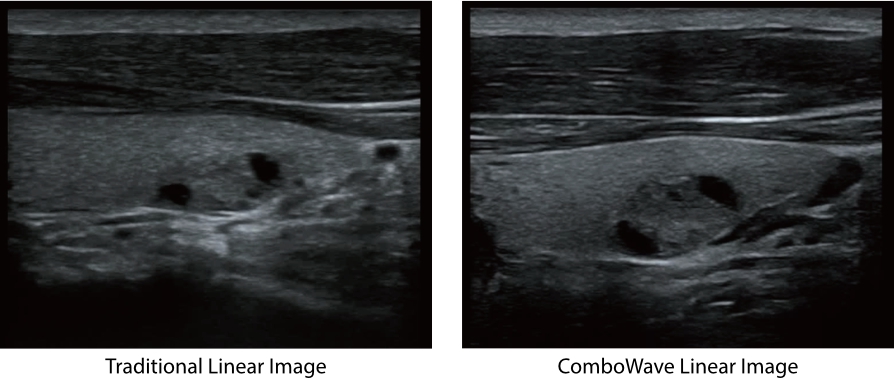

Transductores ComboWave

En comparaciĂłn con los sensores tradicionales, los transductores ComboWave utilizan un nuevo tipo de material piezoelĂ©ctrico compuesto que optimiza notablemente el espectro acĂșstico y reduce la impedancia acĂșstica. AdemĂĄs de integrarse con la tecnologĂa Ășnica 3T de Mindray, los transductores lineales ComboWave ofrecen un rendimiento sobresaliente con una gran uniformidad y resoluciĂłn de imagen en ecografĂas vasculares, de tiroides, de mama, etc.